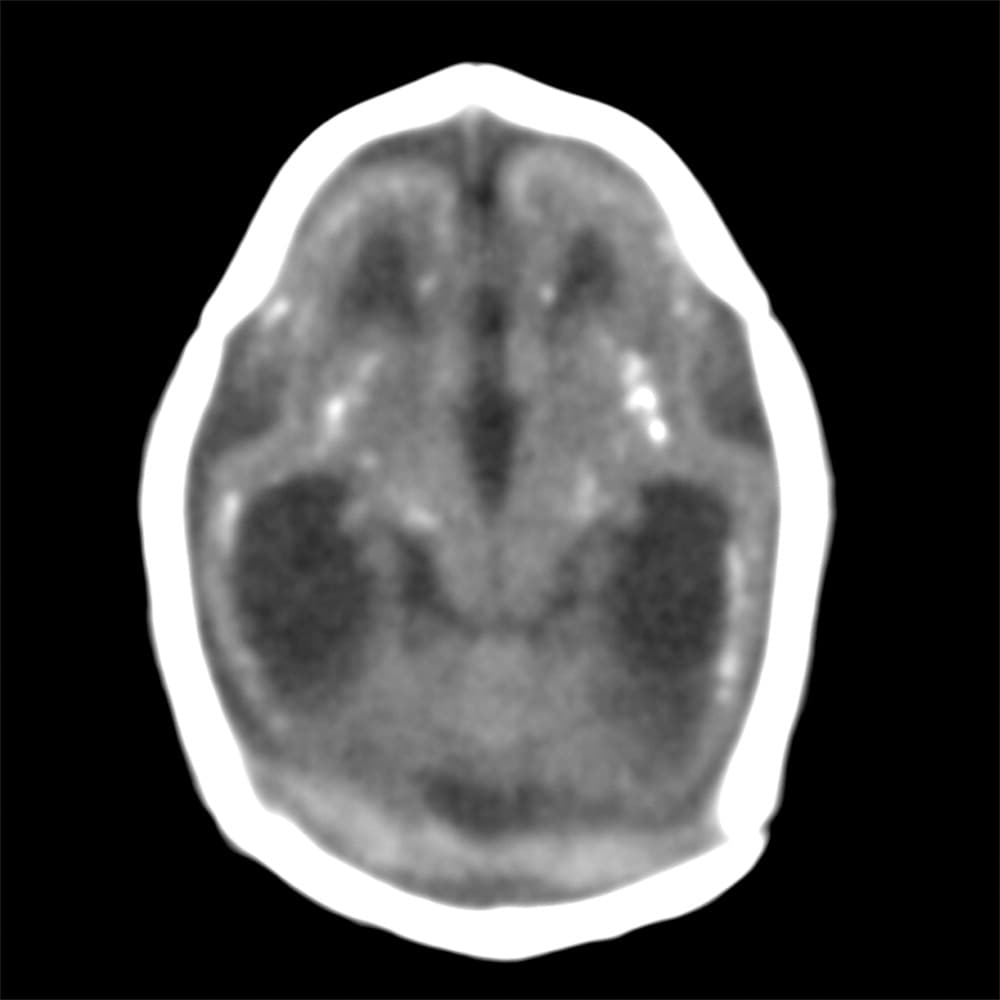

Investigadores brasileños difundieron este martes el mayor número hasta ahora disponible de imágenes computarizadas, resonancias magnéticas y ultrasonidos, de bebés y fetos infectados con el virus del Zika. El daño es mucho mayor del que anticipaban.

Así describe la radióloga brasileña Fernanda Tovar-Moll lo que vio al analizar centenares de imágenes computarizadas, resonancias magnéticas y ultrasonidos de 45 bebés que se contagiaron de zika en el vientre materno en el estado de Paraíba, en el noreste del país, donde el brote ha sido severo.

La mayoría nació con microcefalia, cuya característica más llamativa es que tienen el cerebro y la cabeza más pequeña. Pero muchos sufren una escala y severidad de daño mucho peor en partes importantes del cerebro como el cuerpo calloso, que conecta los dos hemisferios; el cerebelo, que juega un papel significativo en el movimiento, equilibrio y habla; y los ganglios basales, que controlan el pensamiento y la emoción.

Tovar-Moll es coautora de un estudio publicado el martes en la revista Radiology y fue liderado por la doctora Patricia Soares de Oliveira-Szejnfeld, a quien se le da crédito por establecer el vínculo entre el zika y la microcefalia en Brasil.